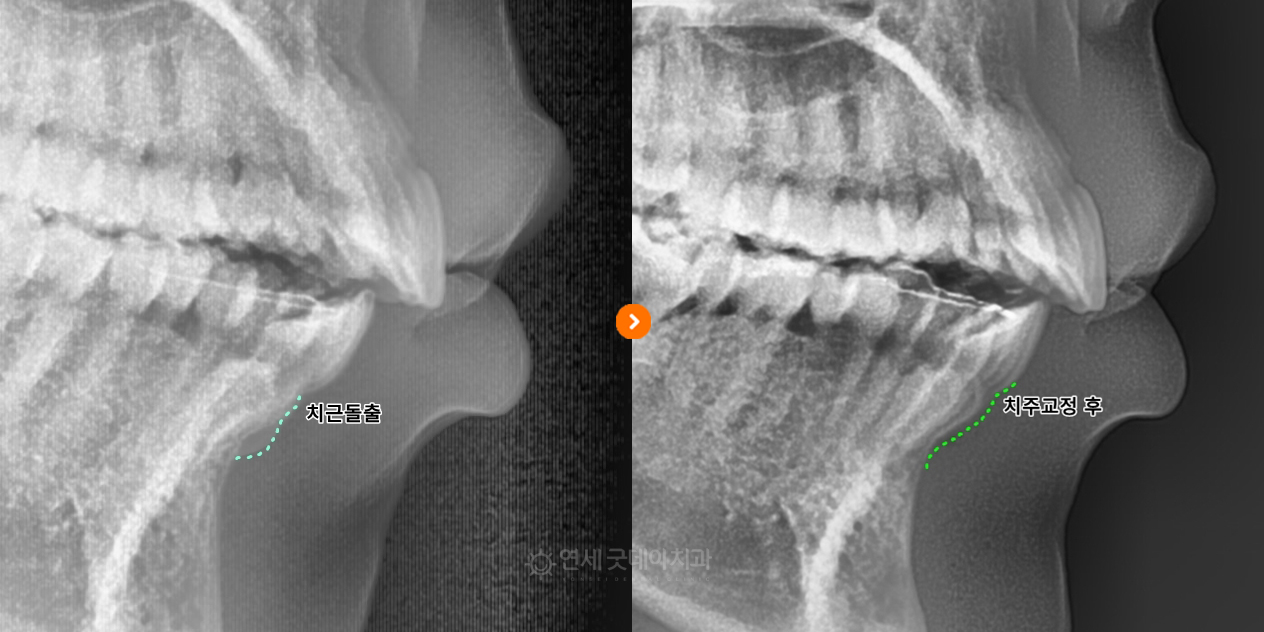

![]() ▲ 치주교정 치료전후 엑스레이 변화 (촬영시기 : 2024년 10월 / 2025년 8월) 엑스레이에서도 치료 전에는 하얗게 돌출되어 보이던 치근이